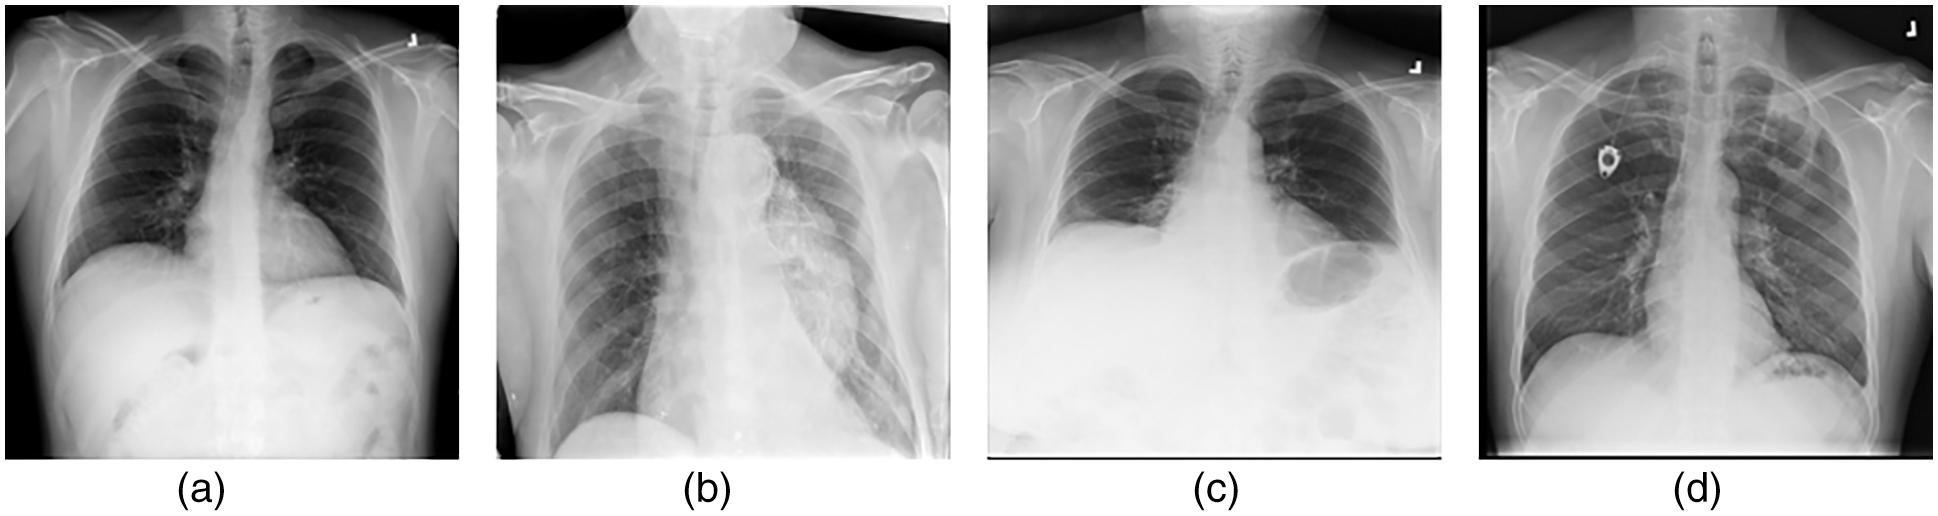

• Lung opacity: individuals with types of cysts that become lodged in the lungs after finding an environment in which to become lodged and cannot be detected by specialists. Fig. 1 images with examples of four different classes are also included.

Figure 1: (a) Normal (b) Covid-19 (c) Pneumonia (d) Lung opacity